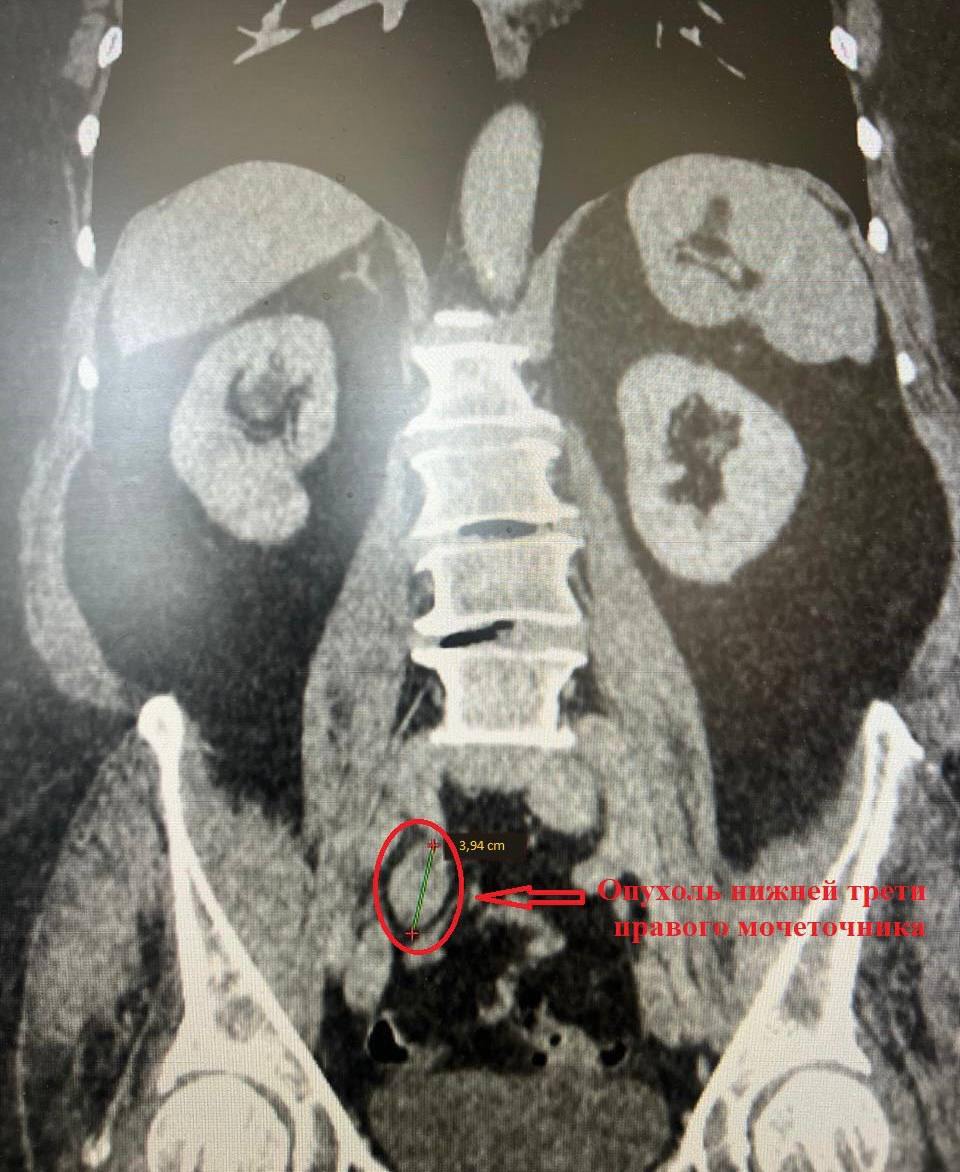

63-летнюю пациентку доставили в Коломенскую больницу с кровотечением. У неё обнаружили опухоль мочеточника, осложнённую ожирением и болезнью почек.

Чтобы избежать удаления органа и пожизненного диализа, врачи провели редкую лапароскопическую операцию: удалили поражённый участок и восстановили мочеточник по методике Боари.